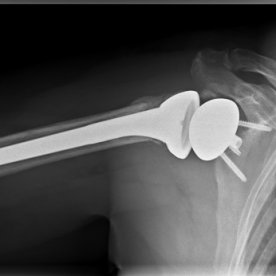

Röntgenbilder